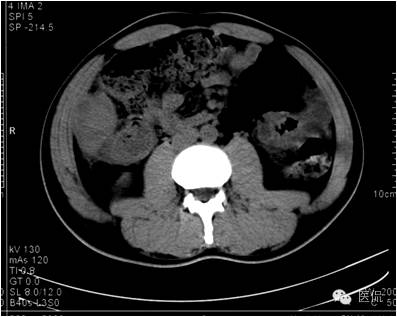

动脉期病灶显示小片状低密度影内,见不规则环状、核心样点状和间隔轻度强化,形态多种。

门脉期上述部位持续强化,程度加重,且环壁影增厚,核心样结节、分隔明显。

延迟期密度略有下降,但仍有强化,形态不规则。